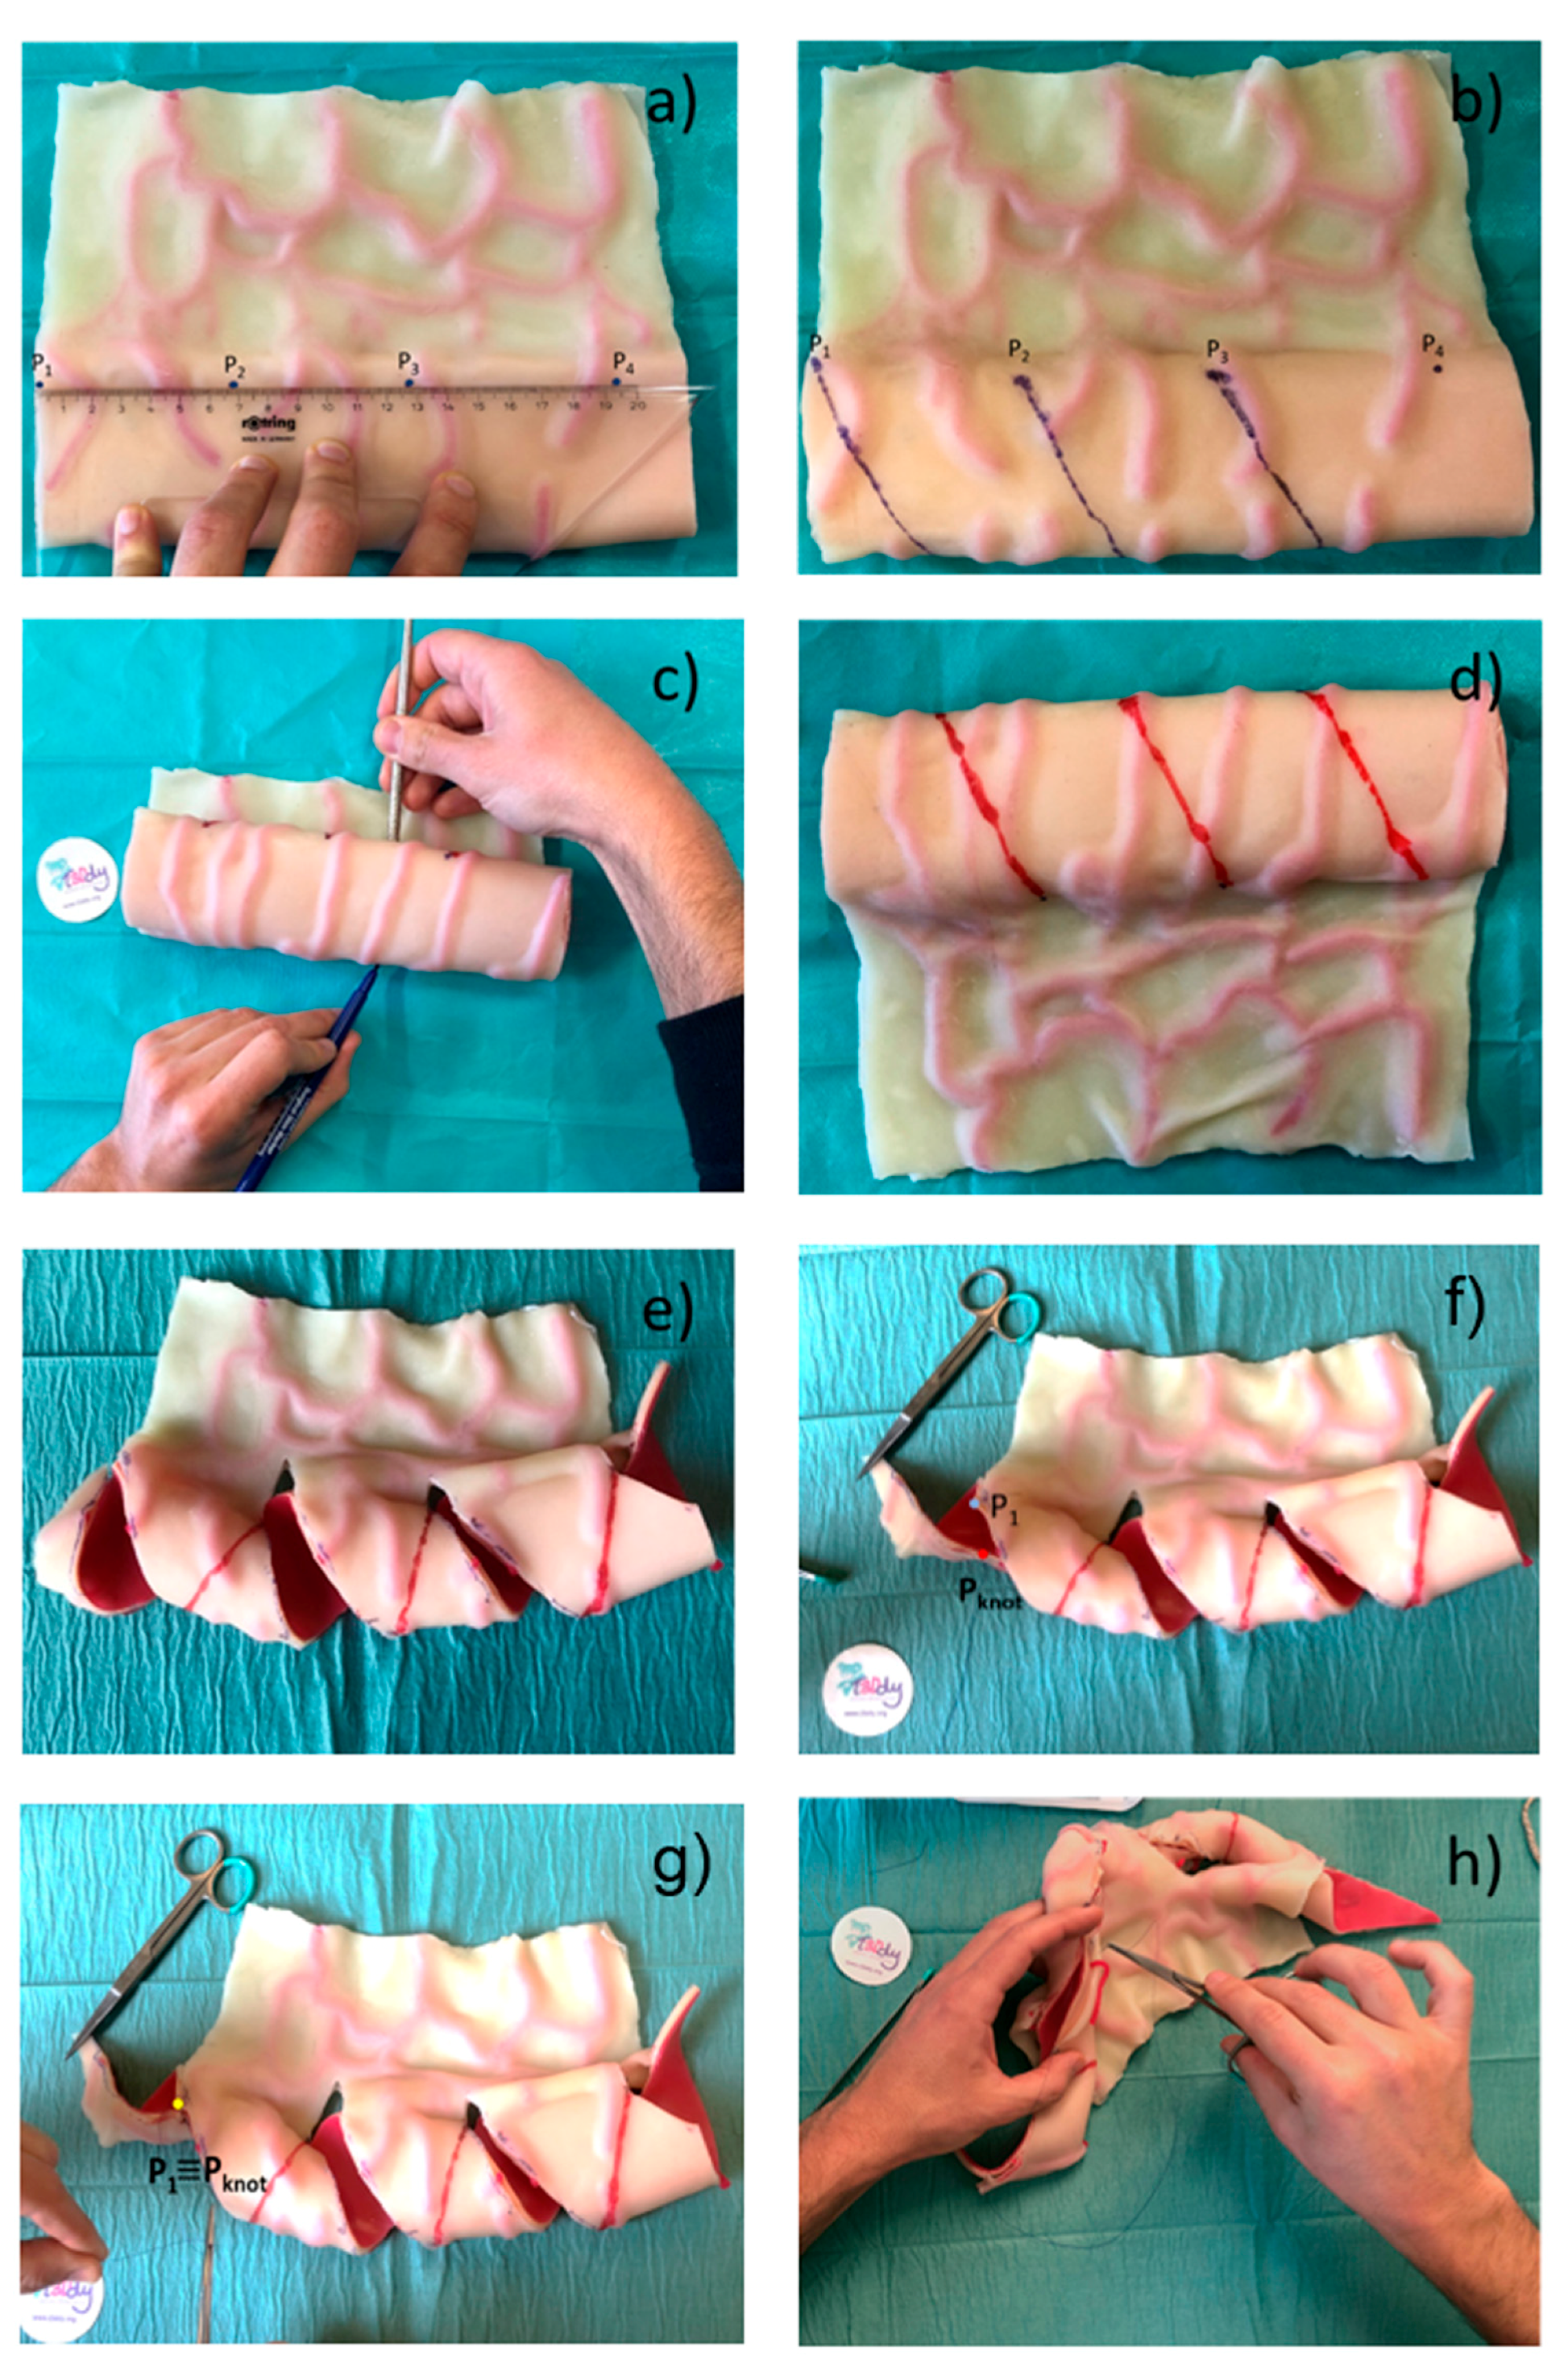

2.2. Surgical Feasibility